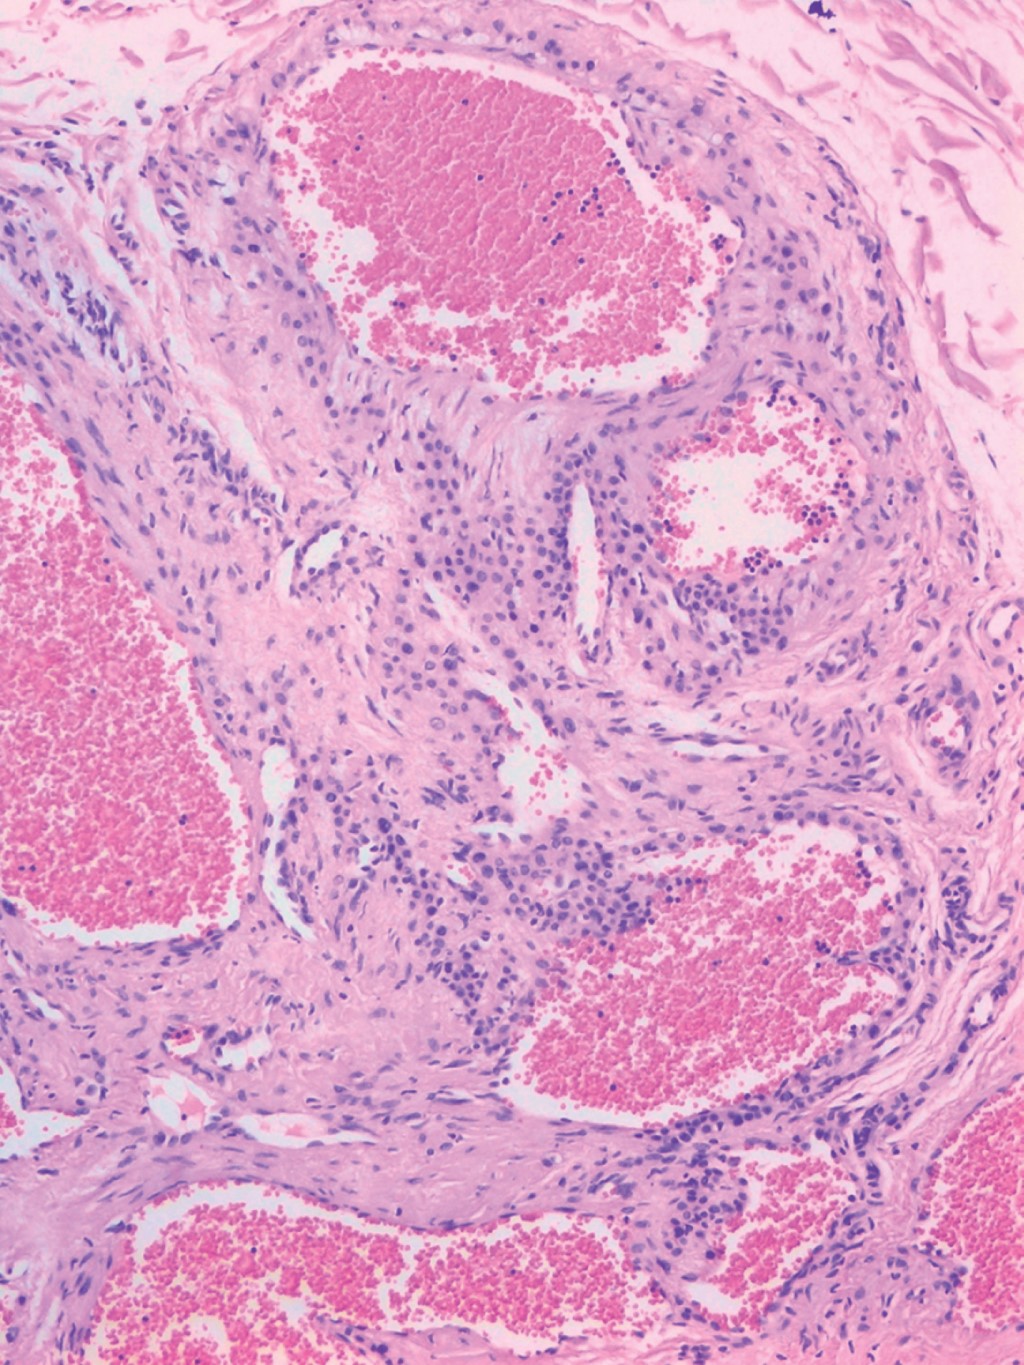

Se hizo biopsia escisional de ambas lesiones; las imágenes del estudio histopatológico se muestran en las Figuras 5 y 6.

El diagnóstico se basa en las características de topografía, morfología y sintomatología acompañante, y se confirma mediante la realización de una biopsia. En la histopatología se observan células glómicas, vasos sanguíneos y músculo liso; según el componente que predomine pueden categorizarse como TG sólido (pocas estructuras vasculares y células musculares escasas), glomangioma (con componente vascular prominente) o glomangiomioma (con predominio del componente vascular y de células musculares lisas). Los TG sólidos son el subtipo más frecuente (73%), seguidos de los glomangiomas (25%). Los TG se tiñen positivo para la actina (marcador de músculo liso).2,4,10

Figura 5

Figura 6